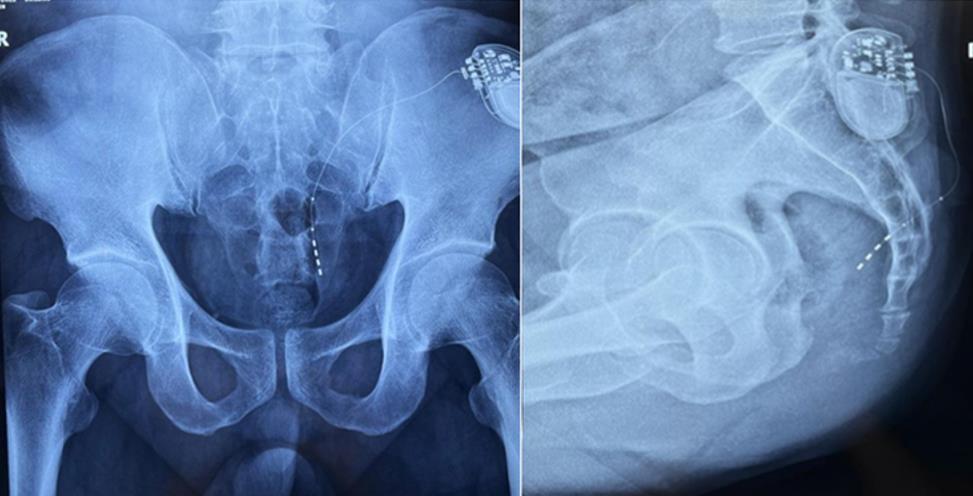

該患者兩年前被診斷患有膀胱過度活動癥(OAB),出現(xiàn)嚴重尿頻、尿急、尿細線等癥狀,醫(yī)生為其做了骶神經(jīng)調(diào)控手術。近期,患者癥狀又開始加重,生活質(zhì)量受到影響,為減輕癥狀,改善生活,患者前往南醫(yī)大二附院就診。衛(wèi)中慶主任及其團隊在查看患者病情后,決定重新調(diào)整電極刺激位置,將刺激點由原左側(cè)骶4神經(jīng)孔改為骶3神經(jīng)孔,通過新的神經(jīng)調(diào)節(jié)順利地改善了癥狀。

患者術前影像

大平板一體式移動C形臂術中影像

在骶神經(jīng)調(diào)控術或者骶神經(jīng)刺激術(SNS)中,醫(yī)師首先會在透視引導下把電極通過導針插入到骶3神經(jīng)孔位置,通過脈沖電流的刺激,達到興奮神經(jīng)纖維并抑制逼尿肌收縮。在這一步,醫(yī)師會先對患者的神經(jīng)刺激反應做測試評估,如果刺激效果明顯,說明該方案能夠達到手術預期。接下來醫(yī)師會在附近皮下脂肪處植入一塊脈沖電流發(fā)生器并與電極相連,使該部位今后能得到長期的電刺激,改善OAB癥狀。